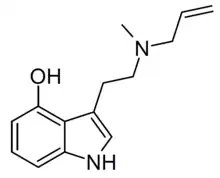

Substituted tryptamines, or serotonin analogues, are organic compounds which may be thought of as being derived from tryptamine itself. The molecular structures of all tryptamines contain an indole ring, joined to an amino (NH2) group via an ethyl (−CH2–CH2−) sidechain. In substituted tryptamines, the indole ring, sidechain, and/or amino group are modified by substituting another group for one of the hydrogen (H) atoms.

| MALT | artificial | H | CH3 | H2C=CH-CH2 | N-methyl-N-allyltryptamine | 1366416-29-6 |

| 4-HO-MALT[5] | artificial | 4-OH | CH3 | H2C=CH-CH2 | 4-hydroxy-N-Methyl-N-allyltryptamine | |

| 4-AcO-MALT [6] | artificial | 4-OCOCH3 | CH3 | H2C=CH-CH2 | 4-acetoxy-N-Methyl-N-allyltryptamine | |

| 4-HO-DALT | artificial | 4-OH | H2C=CH-CH2 | H2C=CH-CH2 | 4-hydroxy-N,N-diallyltryptamine | |

| 4-AcO-DALT | artificial | 4-OCOCH3 | H2C=CH-CH2 | H2C=CH-CH2 | 4-acetoxy-N,N-diallyltryptamine | 1445751-71-2 |

| 5-MeO-MALT | artificial | 5-OCH3 | H2C=CH-CH2 | CH3 | 5-methoxy-N-Methyl-N-allyltryptamine | 1373918-64-9 |

| 5-MeO-DALT | artificial | 5-OCH3 | H2C=CH-CH2 | H2C=CH-CH2 | 5-methoxy-N,N-diallyltryptamine | 928822-98-4 |